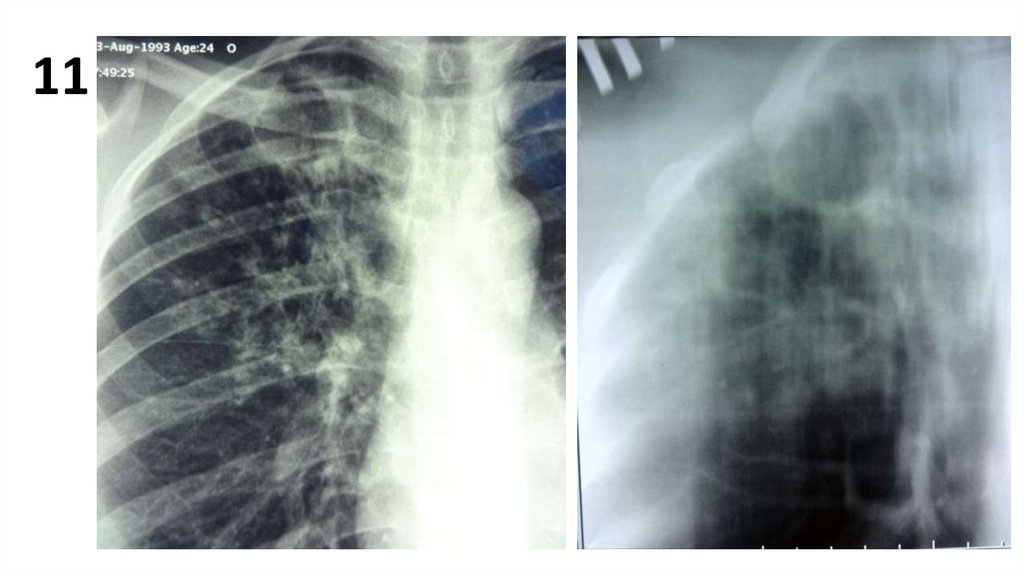

11

13.